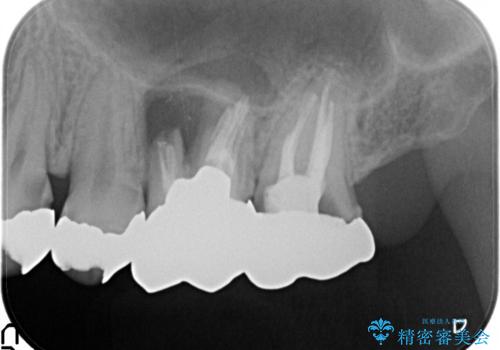

X線検査の結果、左上6には歯根破折、左上7には銀歯の下に大きな虫歯の再発が認められ共に抜歯をせずには症状の改善が見込めない状況です。

奥歯を2本失ったのち、しっかりと噛める環境へと整備するため、しっかりと骨の造成を行い清掃性を高めたインプラント治療を行っていくこととしました。